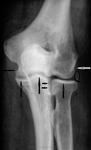

В локтевом суставе артроз проявляется только при чрезмерных двигательных функциональных перегрузках и в основном после предшествовавшей травмы (рис. 8).

Рис. 8. Артроз в стадии остеохондроза правого локтевого сустава.